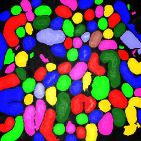

Figure 4 provides an alternative way to show the segmentation results. In particular, yellow regions correspond to true positives which are pixel locations that are identified as tubules in both the groundtruth and segmentation results. Green regions correspond to false positives which are pixel locations that are identified as background in groundtruth but tubules in segmentation results. Similarly, red pixels correspond to false negatives, namely pixel locations identified as tubules in the groundtruth but background in segmentation results, and black pixel regions correspond to true negative that are identified as background in both groundtruth and segmentation results. The green regions indicate Type-I error (false alarm) regions and the red regions represent Type-II error (miss) regions. As observed from Figure 4, the segmentation results in the first row contained large red regions which mean large regions of tubules were missed. Conversely, the segmentation results shown in the second row contained many green regions indicating many background regions were falsely segmented as tubule regions. In contrast, the segmentation results in the third row had reasonably small green regions and red regions which indicate that the deep learning based segmentation results had higher pixel accuracy with relatively low Type-I and Type-II errors.

For visual evaluation we provide the segmentation results of the proposed method using two different datasets: and , sampled at different depths within the volumes. The first row shows original microscopy images , , and from and the second row displays the segmentation results corresponding to the first row. To better visualize the segmentation results, we highlighted individual tubules with different colors and overlaid them onto the original microscopy images. Similarly, the third row exhibits original microscopy images , , and from . Their corresponding segmentation results are shown in the fourth row. Note that the model which was trained on was used for during the inference stage. Although the shape, size, and orientation of tubular structures presented in are all different from , the proposed method can still successfully segment and identify individual tubules presented in as well as individual tubules in .